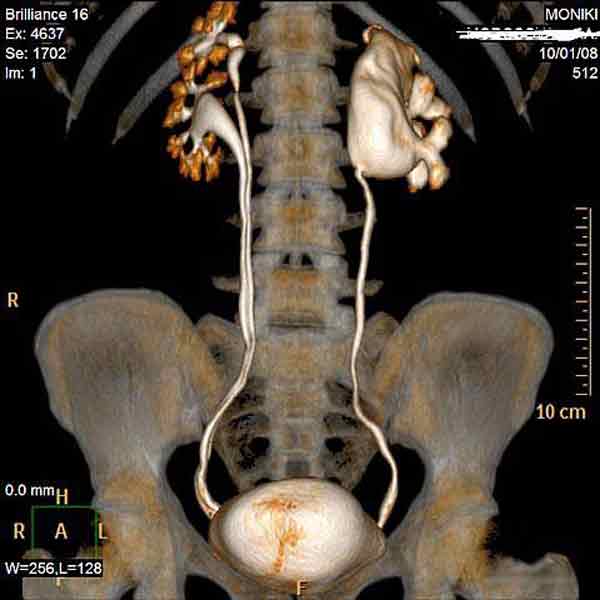

Гидронефроз. Диагностирование и лечение гидронефроза.

Заболевание гидронефроз относится к урологическим болезням. Под гидронефрозом в медицине понимают дисфункцию почки, связанную с расширением ее чашечек и лоханки и прогрессирующим истончением почечной ткани. Причина развития гидронефроза – нарушение оттока мочи из почек, как правило, гидронефроз является следствием или осложнением некоторых других заболеваний.

Гидронефроз может быть односторонним или двусторонним в зависимости от его локализации в парном органе – почках. Он может быть также первичным (вследствие аномалии развития верхних мочевых путей) и вторичным (развивающимся как осложнение какого-либо заболевания).

Диагностирование заболевание требует УЗИ почек и осмотра у квалифицированного уролога. Симптоматика гидронефроза размыта, это могут быть боли в спине, кровь при мочеиспускании). Медицинский центр «Твой Доктор» предлагает комплексное обследование мочевыводящих путей – УЗИ почек, доплерография сосудов почек, рентгеновские исследования, различные лабораторные анализы. Собственная лаборатория медцентра позволяет быстро и качественно провести лабораторную диагностику заболевания с последующим лечением.